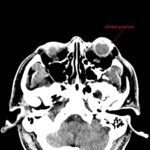

Physical exam showed marked left palpebral subcutaneous crepitus, as well as bulbar and palpebral conjunctival bulging. Visual acuity was normal with intact extraocular movements, and normal pupillary exam. Computed tomography (CT) imaging of the face was obtained and revealed multiple displaced fractures involving the left orbital floor and zygomatic arch associated with moderate periorbital and postseptal extraconal gas, resulting in orbital proptosis.